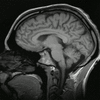

العلوم العصبية هي الحقل الذي يدرس و يتعامل مع البنى العصبية , الوظائف العصبية , التطور العصبي , علم الجينات , الكيمياء الحيوية , الفيزيولوجيا , علم الأدوية , إضافة إلى علم الأمراض العصبي . يطلق عليه أيضا اسم البيولوجيا العصبية حيث يندرج ضمن الطب و يدرس الظواهر المخية. فقد أكتشف مثلا أن عدد الخلايا المخية لا يتغير تقريبا مع الزمن ولكن الذي يتغيير هو كيفية تواصل و تلاحم هذه الخلايا. فكلما درب المرء نفسه و أجهد دماغه بالتفكير كلما زاد عدد الوصلات و إلتحامها و هو ما يؤدي إلى مقدرة أكبر على الإستيعاب و الذكاء و العكس بالعكس. الدراسة البيولوجية للدماغ البشري يشكل أساس هذا الحقل المتداخل الذي يتضمن العديد من مستويات الدراسة , من المستوى الجزيئي إلى المستوى الخلوي (العصبونات المفردة) , إلى مستوى التجمعات الصغيرة نسبيا من العصبونات مثل cortical columns , و الجمل الفرعية الأكثر تعقيدا مثل ساحات الإدراك البصري visual perception , و حتى الجمل العصبية الضخمة مثل القشرة المخية cerebral cortex و المخيخ cerebral cortex كأعلى مستويات التعقيد ضمن الجهاز العصبي . |